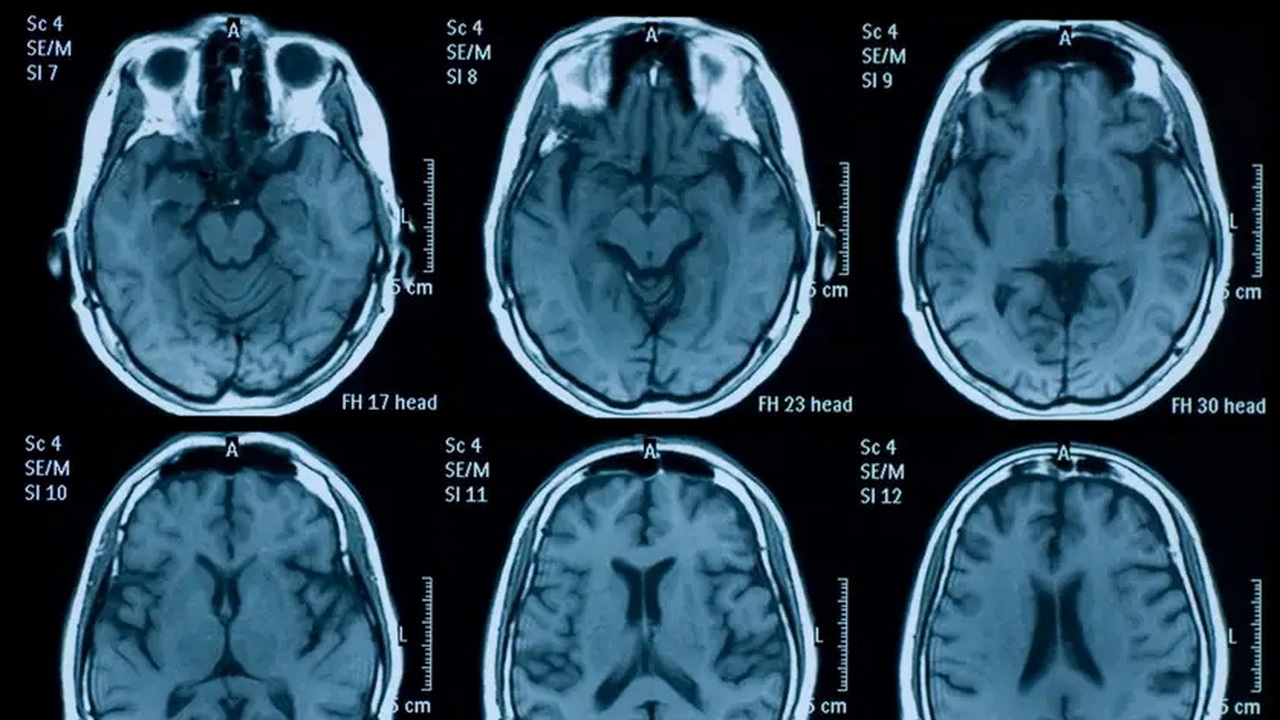

Η ομάδα επεξεργάστηκε εγκεφαλικές μαγνητικές τομογραφίες σχεδόν 1.000 ενηλίκων, συγκρίνοντας άτομα που σάρωσαν τον εγκέφαλό τους πριν και μετά την πανδημία με εκείνα που πραγματοποίησαν σάρωση μόνο προ πανδημίας, ώστε να εντοπιστεί διαφορά στον ρυθμό γήρανσης του εγκεφάλου, βασιζόμενη στο πόσο «ηλικιωμένος» έμοιαζε ο εγκέφαλος σε σχέση με την πραγματική ηλικία των συμμετεχόντων.

Οι αλλαγές αυτές ήταν πιο έντονες στους μεγαλύτερους ηλικιακά, στους άνδρες και σε ανθρώπους με κοινωνικοοικονομικές δυσκολίες. Είναι αξιοσημείωτο πως μόνο όσοι μολύνθηκαν από COVID-19 παρουσίασαν μετρήσιμη μείωση σε ορισμένες γνωστικές λειτουργίες – όπως η ταχύτητα επεξεργασίας πληροφοριών – ενώ για τη γενική αύξηση της «εγκεφαλικής ηλικίας» λόγω της πανδημίας δεν παρατηρήθηκαν άμεσα συμπτώματα.

Οι ειδικοί, ωστόσο, επισημαίνουν ότι οι μεταβολές μπορεί να είναι αναστρέψιμες και ενθαρρύνουν τη συνέχιση της έρευνας, καθώς τα ευρήματα δείχνουν πως μεγάλες περίοδοι κοινωνικής αβεβαιότητας και στρες μπορούν να αφήσουν αποτύπωμα ακόμα και στον εγκέφαλο υγιών ανθρώπων, τονίζοντας την ανάγκη να προσεγγίσουμε την υγεία του εγκεφάλου ολιστικά και πέρα από τις άμεσες βιολογικές επιπτώσεις μιας ασθένειας.